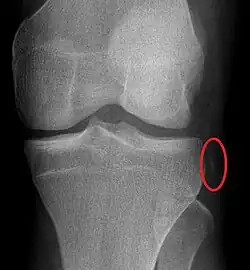

Plain X-rays, CT scan, ultrasonography, or MRI may help with the diagnosis.[2][11] Findings on X-ray that may be useful among those who have already reduced include a variable joint space, subluxation of the joint, or a Segond fracture.[5]